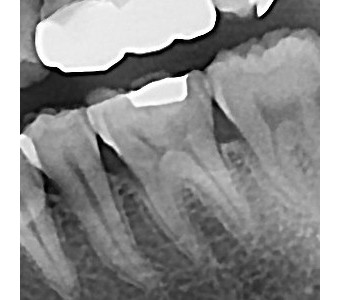

결과로 증명합니다.

국제모아치과의

실제 임상 증례